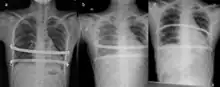

Iatrogenic hemothorax resulting from the Nuss procedure. A showing no hemothorax, b showing hemothorax, and c showing resolution after treatment.

Air in the chest (pneumothorax) is one of the more frequent complications. A chest tube may be required or aggressive breathing exercises and close monitoring may be adequate.

Other complications which may occur include hemothorax, pleural effusion, pericarditis, wound infection and pneumonia and acquired scoliosis.[3]:340 Vigorous incentive spirometry is used to prevent pneumonia.[3]:341 Some patients are allergic to one of the components of stainless steel.[3]:341 As a result, allergy testing is now routinely done prior to surgery. In the event of an allergy, a titanium bar will be used.